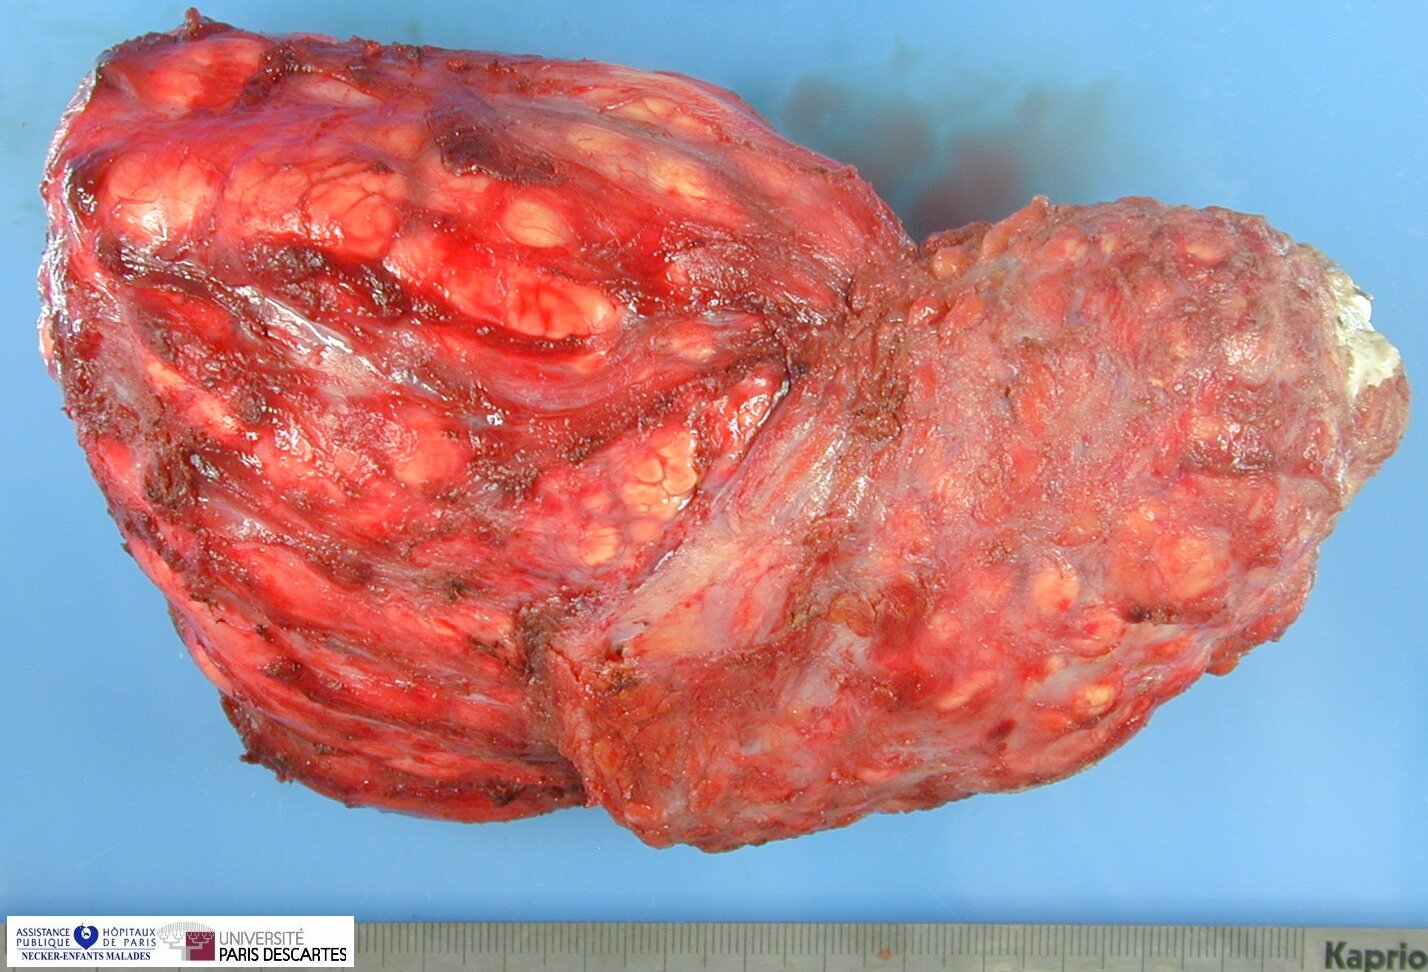

Tumoral Calcinosis